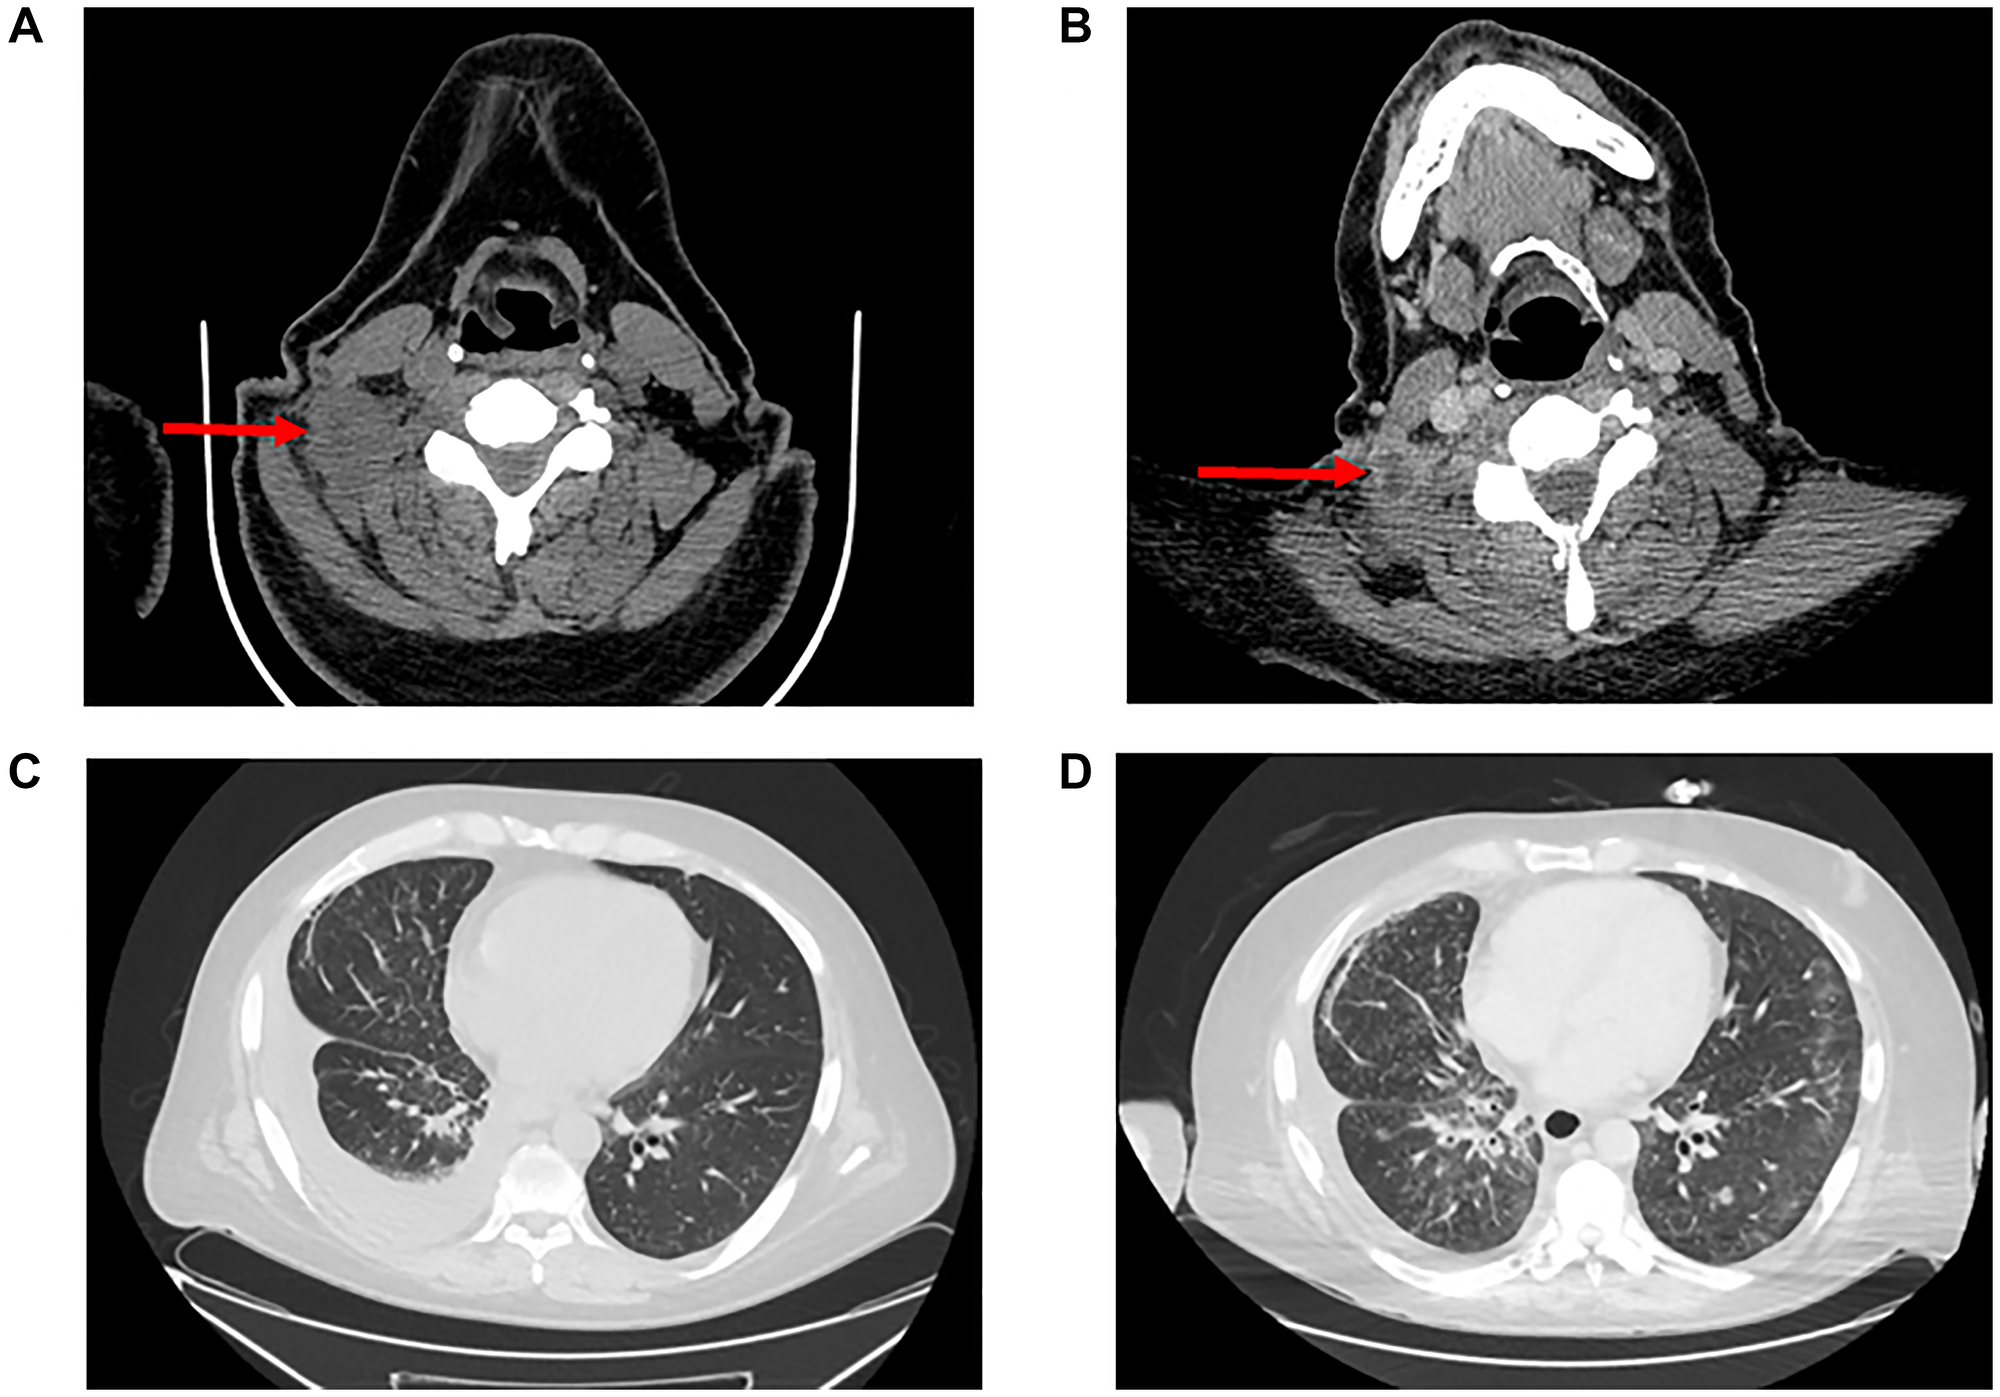

Pralsetinib (400 mg) was added in combination with dose reduced lorlatinib (from 100 mg to 75 mg), and vinorelbine was stopped. The patient had no severe adverse events, and a radiographic response was achieved on CT imaging one month later (Figure 2), with significant decrease in the right cervical lymph node, stable supraclavicular nodes, stable CNS and osseous metastases, and decrease in pulmonary disease and pleural effusion. Two months later, the noted lymph nodes remained stable on repeat imaging. Unfortunately, the patient died suddenly from respiratory failure after 4 months on pralsetinib plus lorlatinib due to disease progression.

Figure 2: Radiographic response imaging to pralsetinib plus lorlatinib.

(A) Computed tomography (CT) during lorlatinib treatment revealing right cervical lymph node. (B) CT showing decrease in lymph node size with necrosis after addition of pralsetinib. (C) Chest CT during lorlatinib treatment showing right-sided pleural effusion. (D) Chest CT showing decrease in effusion after pralsetinib treatment. Images A and C were taken on day 1135 post-diagnosis. Images B and D were taken on day 1268.